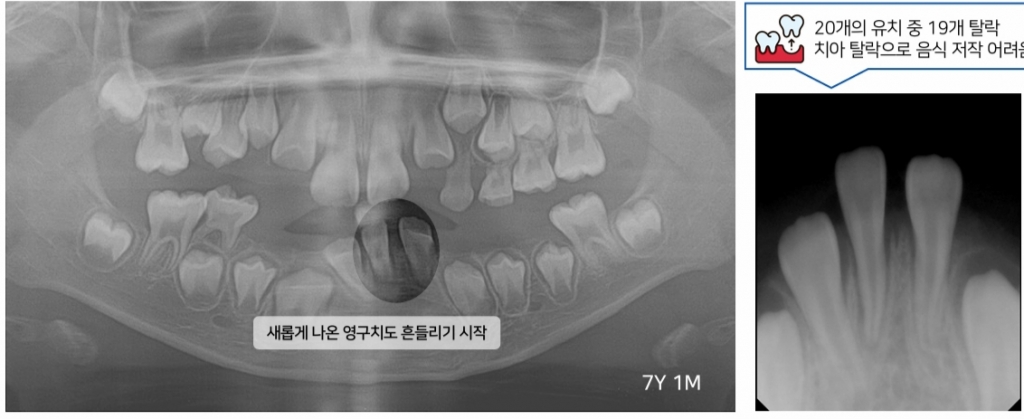

이 때문에 저인산효소증 환자가 1세 이전에 사망할 확률은 58%, 5세 이전 사망률은 73%에 달한다. 2022년 국내 5세 미만 사망 인원(1532명) 가운데 저인산효소증으로 인한 사망자는 6명으로 추정된다. 강정민 연세대 치과대학병원 소아치과 교수는 "저인산효소증으로 유치가 일찍 빠지면 잇몸뼈(치조골)가 흡수돼 치아가 흔들리고 잇몸이 내려앉는다"며 "성장기인데도 음식 섭취가 어려워 성장·발육을 저해하고, 유치원생인데 틀니를 껴야 하는 상황까지 초래한다"고 설명했다.